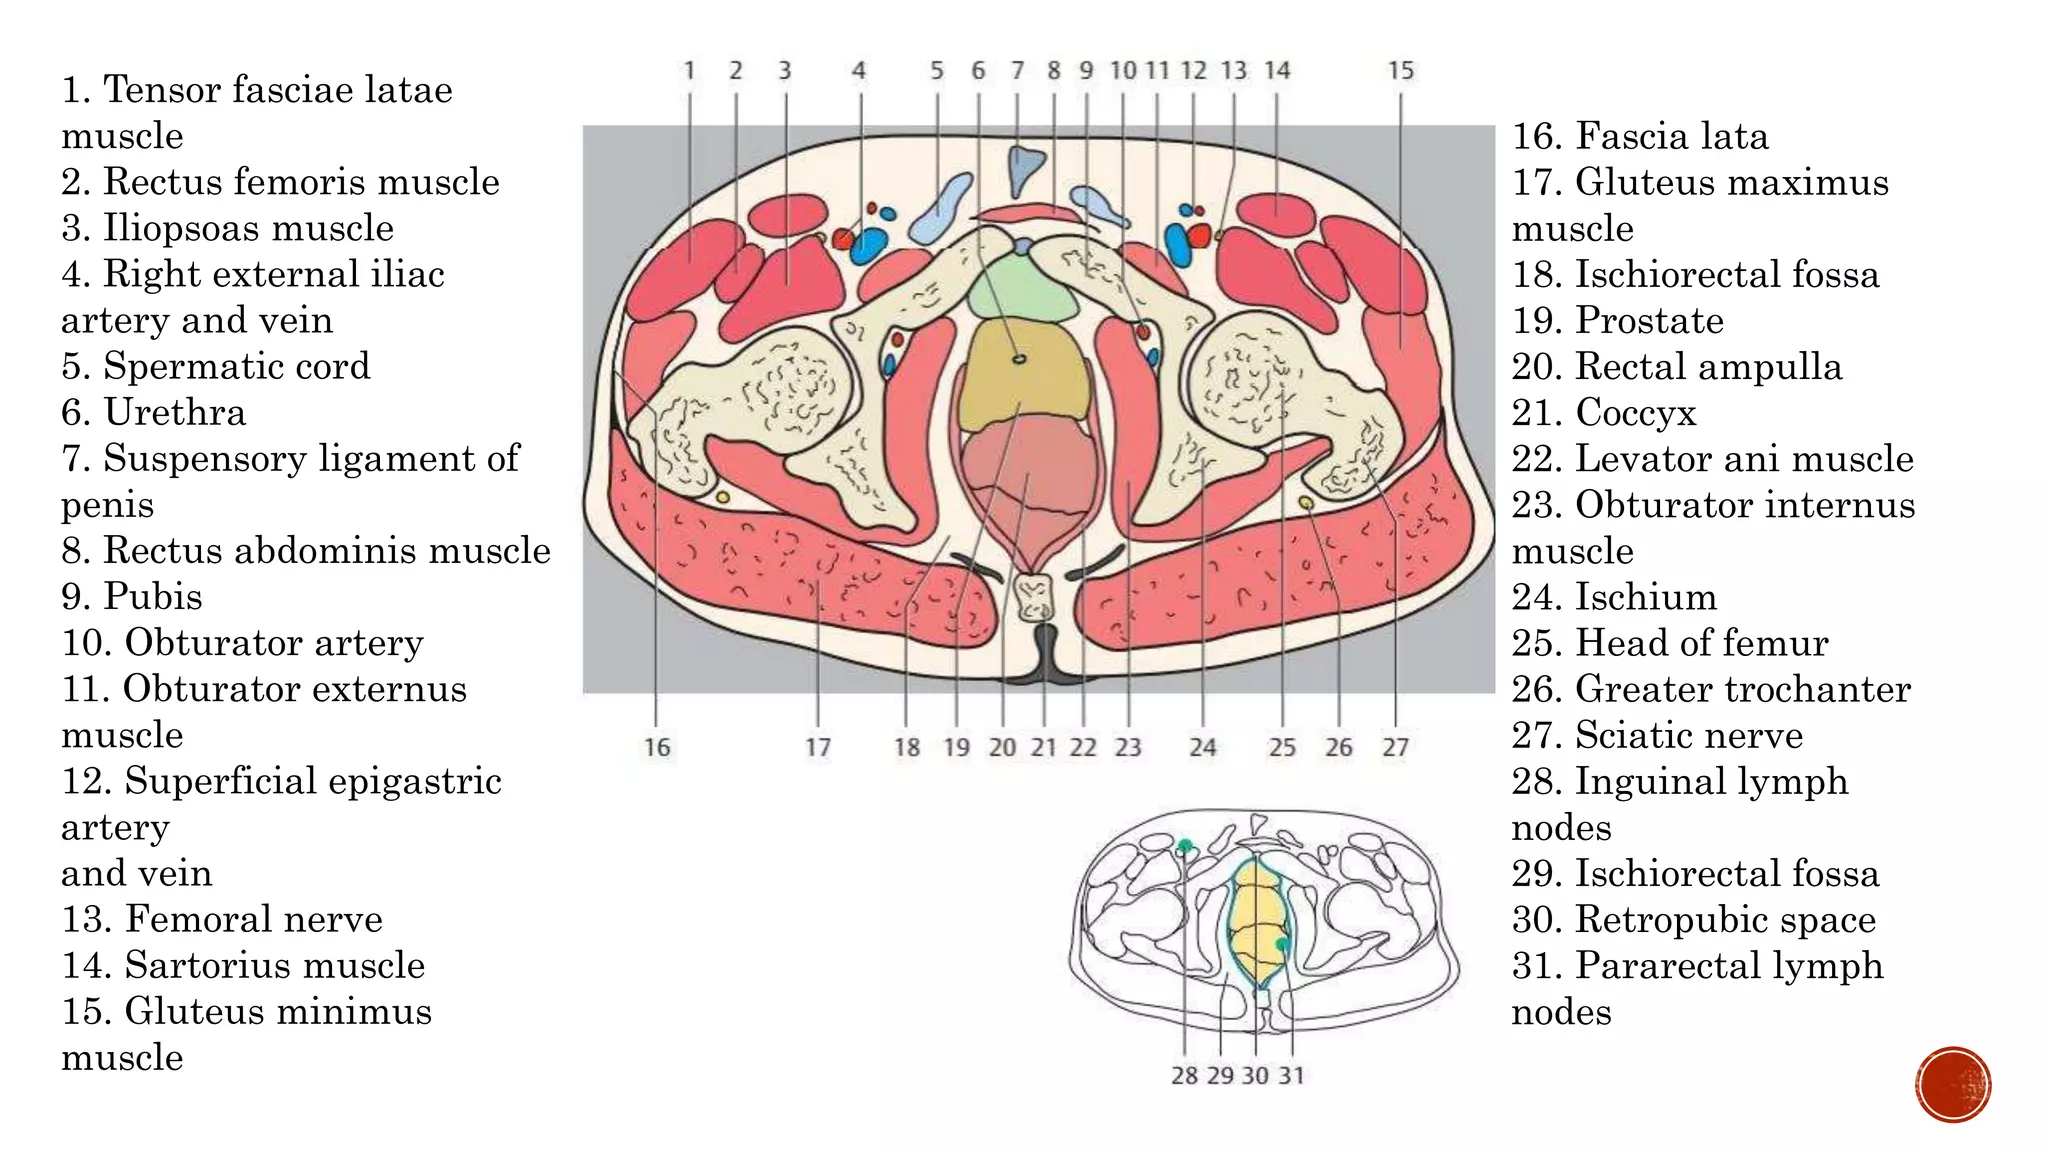

The document describes the anatomy of the abdomen and pelvis region of the human body. It lists over 40 structures and their locations, including major organs like the liver, kidneys, intestines, blood vessels and muscles of the abdominal wall and pelvis. The structures are grouped into sections focusing on different anatomical areas like the abdomen, retroperitoneum, pelvis and gluteal region.